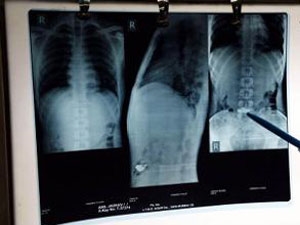

‘ஆன்கிலோசிங் ஸ்பாண்டிலைட்டிஸ்’ எனும் நோயால் முதுகுத்தண்டு பாதிக்கப்பட்டு முடங்கி இருந்த 82 வயது முதியவருக்கு அரிய வகை ஆபரேஷன் செய்து மும்பை மருத்துவர்கள் சாதனை புரிந்துள்ளனர்.

‘பேம்பூ ஸ்பைன்’ என்று பொதுவாக அழைக்கப்படும் இந்த நோய் தாக்கினால் முதுகுத்தண்டு இணைப்பில் தாங்க முடியாத அளவு வலி ஏற்படும். கழுத்தெலும்பு தொடங்கி முதுகுத்தண்டின் நுனி எலும்பு வரை உடைந்து போவது போல் வலிக்கும்.

இதையடுத்து, மும்பையில் உள்ள தனியார் மருத்துவமனைக்கு கடந்த மார்ச் மாதம் அவர் அழைத்து வரப்பட்டார். அவரை தீவிரமாக பரிசோதித்த மருத்துவர்கள் அறுவை சிகிச்சை செய்வது மட்டுமே ஒரே தீர்வு என்று தெரிவித்தனர். ஆனால் வழக்கமான அறுவை சிகிச்சையை 82 வயது முதியவரின் உடல் தாங்கிக் கொள்ளாதென்பதால், அறுவை சிகிச்சையின் போது சதைகளில் ஏற்படும் சேதத்தை வெகுவாக குறைக்கும் minimally invasive spine சர்ஜரியை மேற்கொண்டனர்.

மார்ச் மாத இறுதியில் நடத்தப்பட்ட இந்த அரிய ஆபரேஷனில் முதியவரின் முதுகுத்தண்டில் 14 ஸ்க்ரூக்களைப் பொருத்தி அவரது நோயை குணமாக்கி மருத்துவர்கள் சாதனை புரிந்தனர். தற்போது யார் துணையும் இல்லாமல் வெளியே சென்று வரும் அளவிற்கு முதியவரின் உடல்நிலை முன்னேறியுள்ளதாக மருத்துவர்கள் தெரிவித்துள்ளனர்.